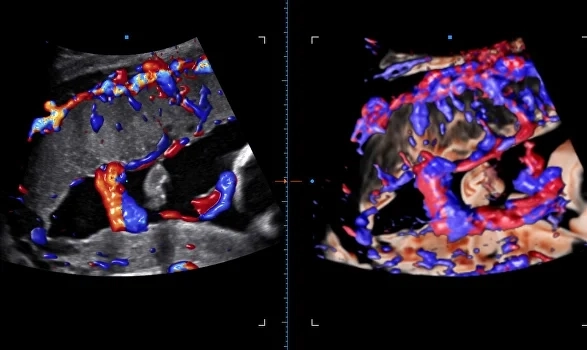

Безупречная картинка в 3D и 4D

Совершенно новый уровень визуализации плода с потрясающим качеством. Samsung Z20 открывает широкие возможности для диагностики и позволяет врачам работать максимально эффективно.